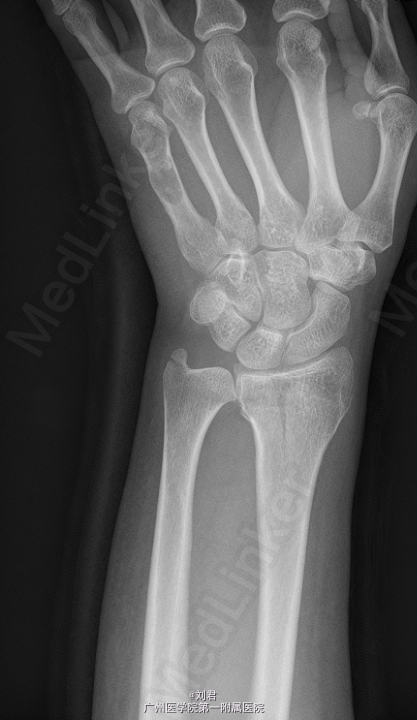

患者,女,51岁,因“摔伤致左腕肿痛伴活动障碍7天”入院。 患者7天前摔伤,左掌着地,致昨晚疼痛,疼痛为持续性,较剧,能忍,伴左腕活动障碍.

左腕石膏托固定,左腕肿胀,无明显畸形,压痛明显,左腕活动障碍,左手各指血运好,感觉正常,活动可。

初步诊断:1、 左桡骨远端骨折,2、左手第5掌骨软骨类肿瘤。在臂丛复合静脉麻醉下行“左掌骨内生软骨瘤切除术”,手术过程顺利,术后予以对症治疗。